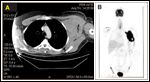

FIGURE 1

Postoperative CT and PET Scans

The patient's postoperative course was complicated by significant bleeding, requiring numerous transfusions. The mass continued to grow very rapidly and a follow-up CT scan, done 3 weeks after the third surgery, showed the left axillary mass to now measure 9.9 X 9.5 cm (Figure 1A). A positron-emission tomography (PET) scan at that time showed hypermetabolic uptake only in the left axilla (Figure 1B).